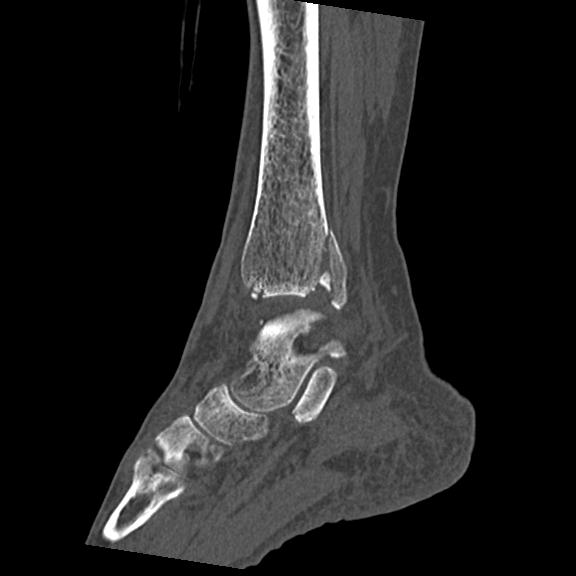

56476 8/28 4R 1/21 2R 左足関節 デジカメ写真 72歳女性 右足関節AS